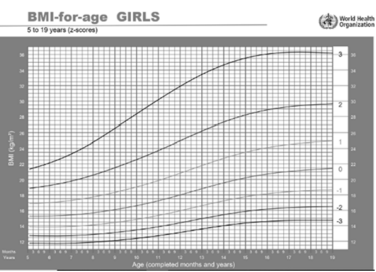

Uma adolescente de catorze anos de idade foi à consulta de rotina sem queixas. Refere que, durante todo o período da pandemia, permaneceu em casa, assistindo às aulas de forma on-line, praticamente sem atividades esportivas ou sociais com as amigas. Na avaliação pondero-estatural: peso = 68 kg e altura = 1,50 m.

Com base nesse caso hipotético e na curva acima, assinale a alternativa que apresenta o diagnóstico nutricional para a adolescente.